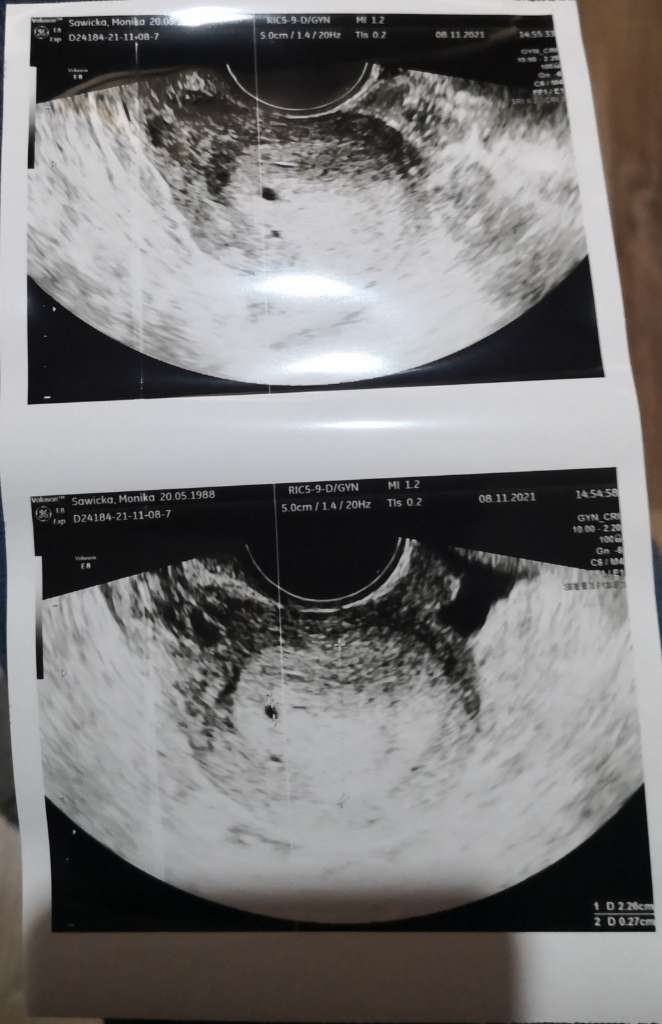

Myślałam, że wczoraj wstawiłam zdjęcie niezidentyfikowanego obiektu w mym ciele, ale widzę że nie, więc nadrabiam. Oglądajcie obcego

![]()

nie pomyślałam, na szybko strzelałam fotę, ale to tylko imię, nazwisko i data urodzeniaRzeczywiscie cos tam jest![]()